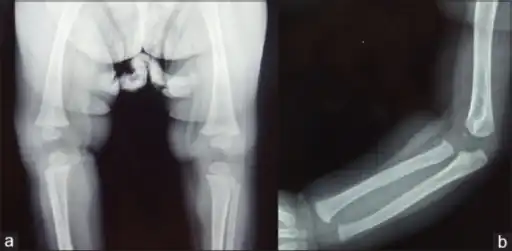

Wimberger corner sign; X-rays of (a) lower limbs (AP view) and (b) upper limbs (AP view) showing resolution of metaphyseal erosions and periosteal reaction

a) X-ray of the lower limb (AP view) showing proximal tibial metaphyseal erosions along with periosteal reaction and (b) X-ray of the upper limb (AP view) showing distal tibial and fibular metaphyseal erosions with periosteal reaction